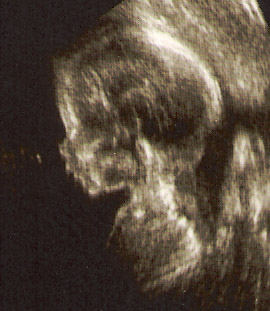

The First Day I Met You

was not August 17, 2006. It was about 4-1/2 months earlier, when you were only about 20 weeks old in Dianna’s womb. For Moms, they know the are pregnant. They can sense the change in their bodies, and feel the new life that is being woven together within them. It affects every aspect of their …